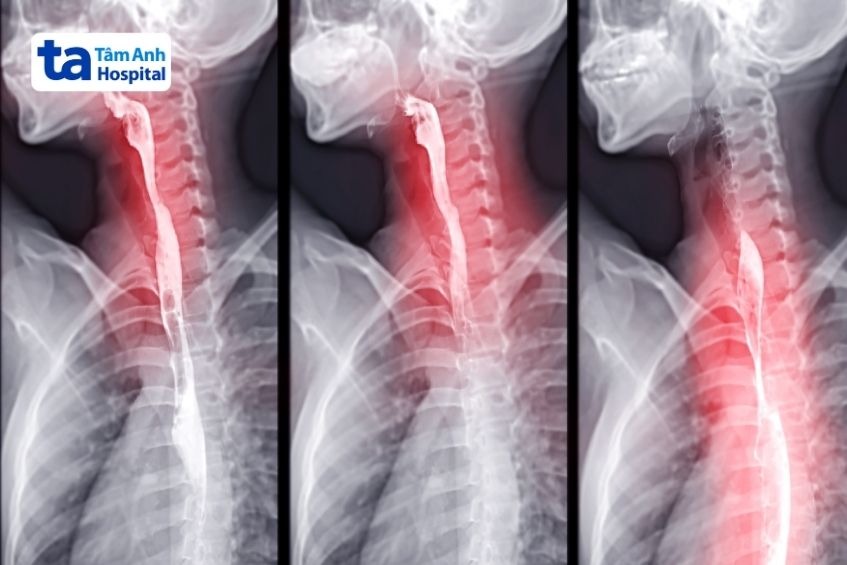

Chụp X-quang ngực cho phép các bác sĩ có thể kiểm tra các dấu hiệu biến đổi ở phổi có thể do axit dạ dày gây ra.

Phương pháp này được sử dụng để kiểm tra các cơ quan ở phần trên của hệ tiêu hóa của trẻ bao gồm thực quản, dạ dày và phần đầu của ruột non (tá tràng). Trước khi thực hiện, trẻ sẽ được cho nuốt một chất lỏng cản quang gọi là bari. Bari giúp làm nổi bật đường tiêu hóa trên hình ảnh X-quang, từ đó các bác sĩ có thể quan sát sự di chuyển của thức ăn qua thực quản và xác định một số nguyên nhân có thể gây ra trào ngược.